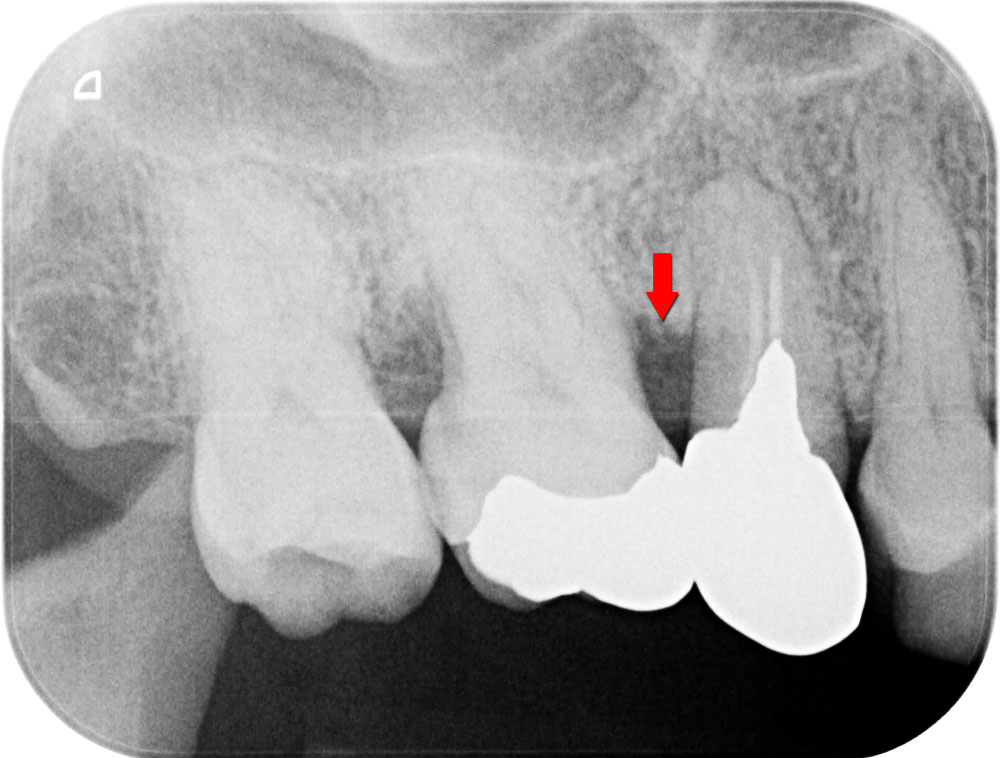

お口全体の徹底した歯石除去をおこないます。その後歯科衛生士による歯ブラシ指導をおこない患者さんのホームケアの質を高めた上で、歯周病の精密検査を行います。基本歯周治療によって歯周病の改善がみられていることを確認のうえ、歯周再生療法に移行します。レントゲン写真の矢印部箇所のように、骨が歯周病により溶けている状態です。